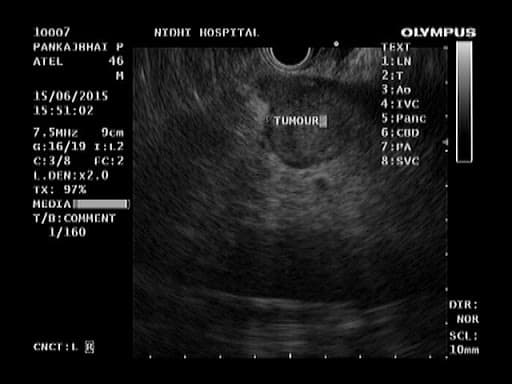

Combines endoscopy and ultrasound for high-resolution imaging

Evaluates pancreas, bile ducts, and GI tract layers

Enables fine needle aspiration (FNA) for tissue diagnosis, cyst drainage, and many other therapeutic procedures

A flexible endoscope which has a small ultrasound device built into to end can be used to see the lining of the esophagus, stomach, small bowel, or colon. The ultrasound component produces sound waves that create visual images of the digestive tract which extend beyond the inner surface lining. Endoscopic ultrasound examinations (also called endoluminal endosonography) may be performed through the mouth or through the anus. EUS is performed under sedation.

EUS provides more detailed pictures of the digestive tract anatomy EUS can be used to evaluate an abnormality below the surface such as a growth that was detected at a prior endoscopy or by X-ray. EUS, because of its ability to examine through the layers of the surface of the GI tract, provides a detailed picture of the growth, which can help the doctor determine its nature and decide on the best treatment.

EUS can also be used to diagnose diseases of the pancreas, bile duct, and gallbladder when other tests are inconclusive, and EUS can be used to determine stage of cancers. Tissue samples can be obtained and certain therapies (such as the removal of certain cysts or aspiration of lymph nodes) can be performed with EUS guidance.